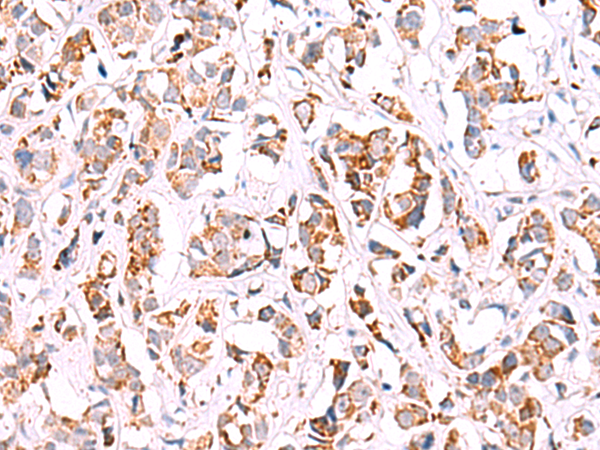

IHC positive control:

Human breast cancer and Human liver cancer

IHC Recommend dilution:

40-200